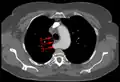

Artère sous-clavière aberrante au scanner axial. (1) trachée, (2) œsophage, (3) Artère sous-clavière aberrante.- Artère sous-clavière droite aberrante à l'angiographie.